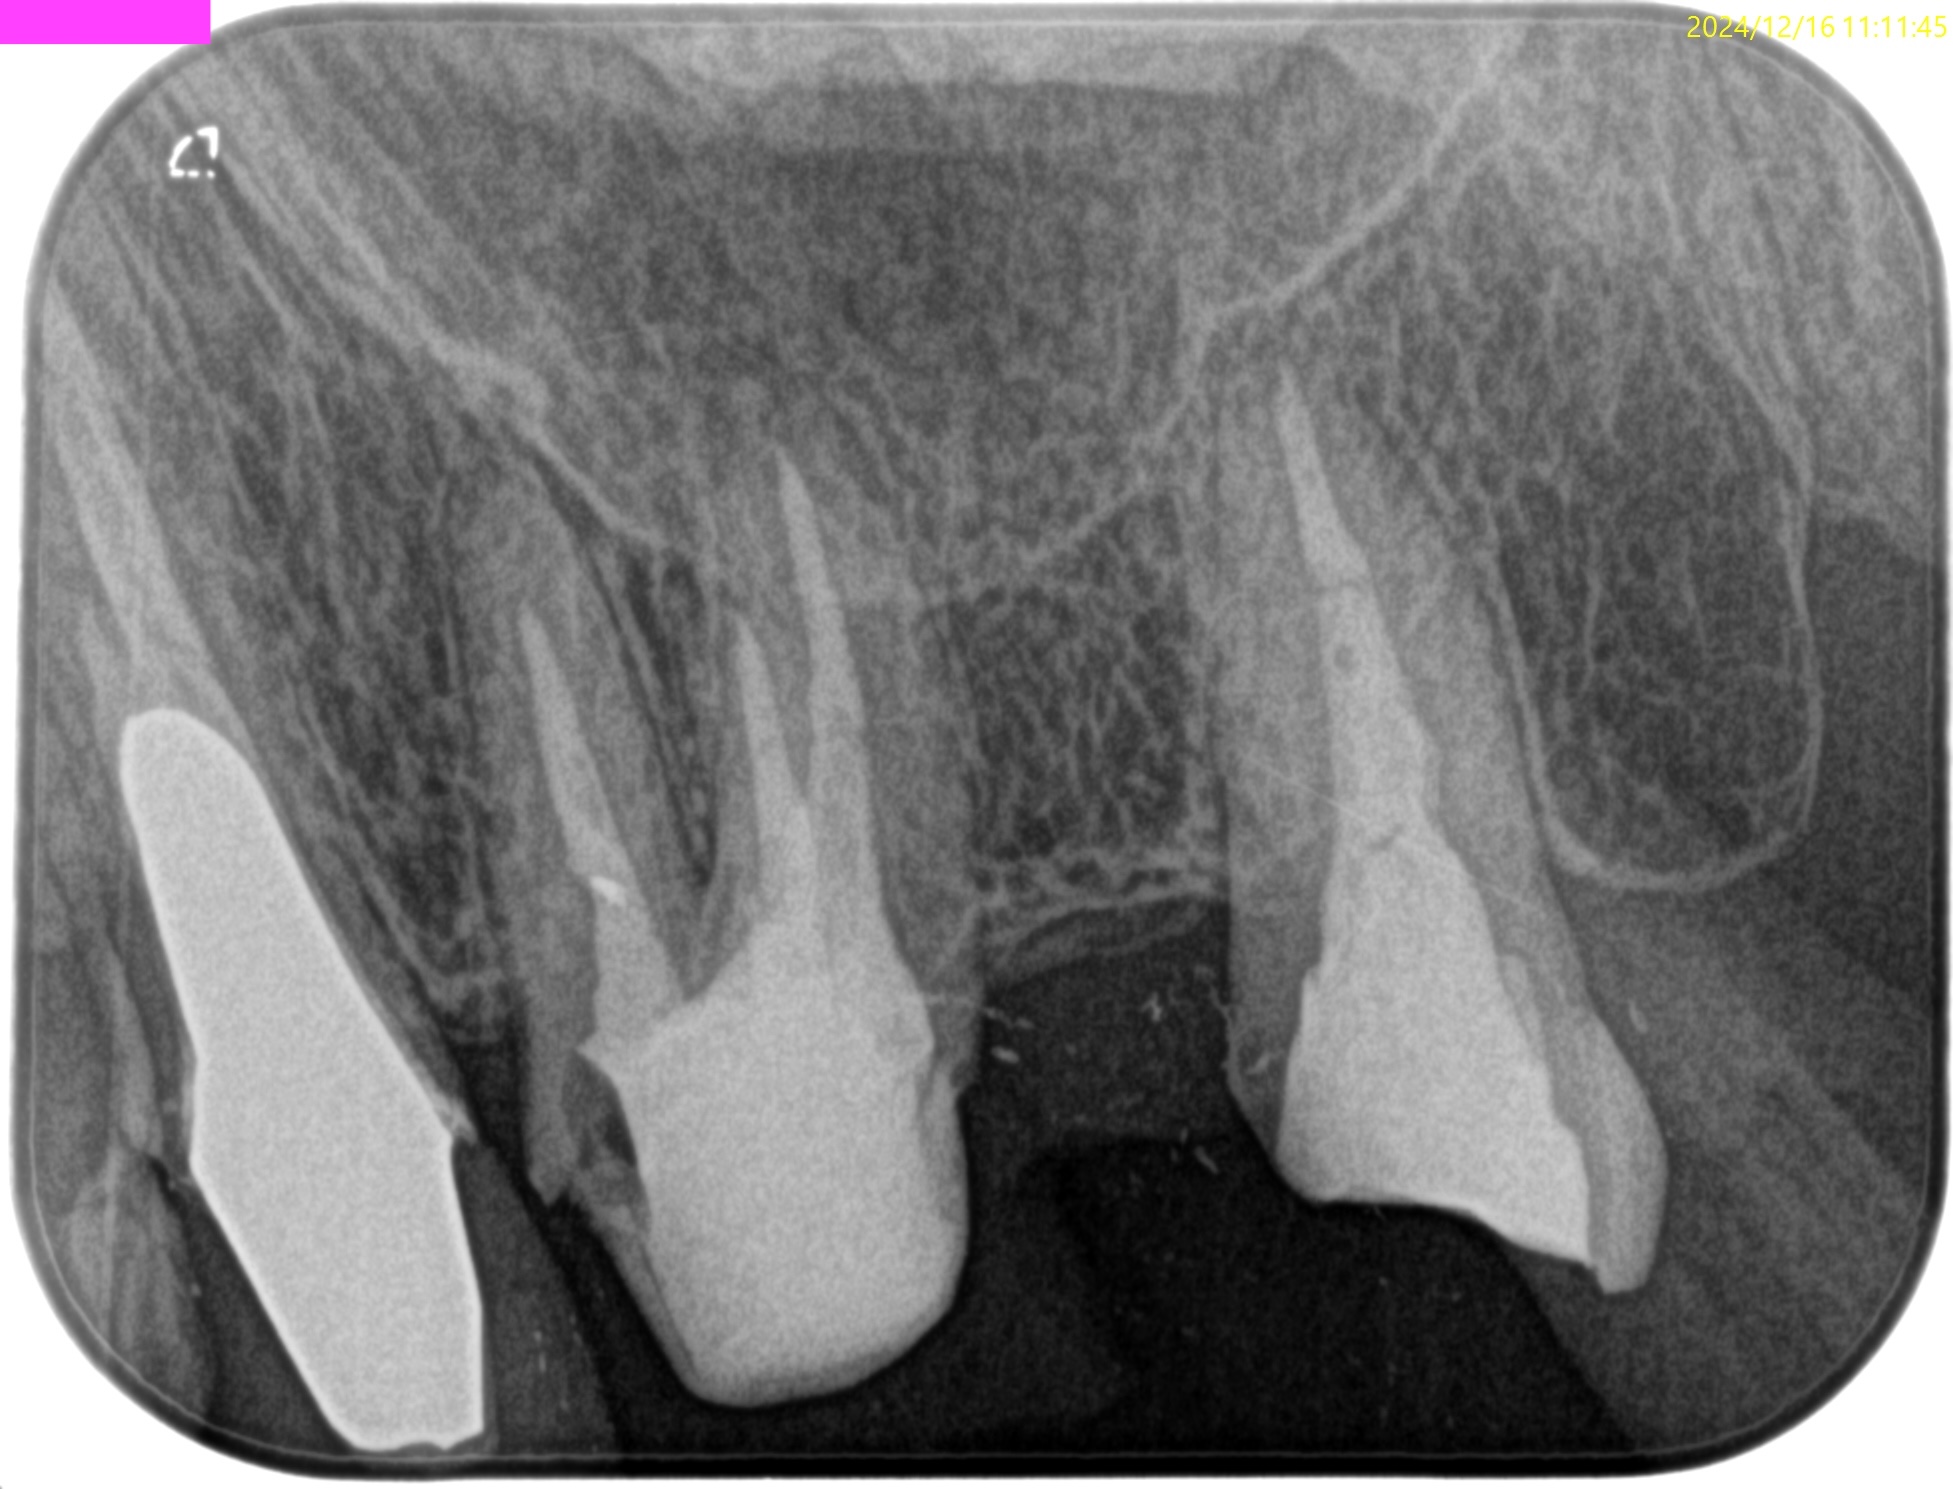

術後にPA, CBCTを撮影した。

#3

MB

DB

P

#14

#16